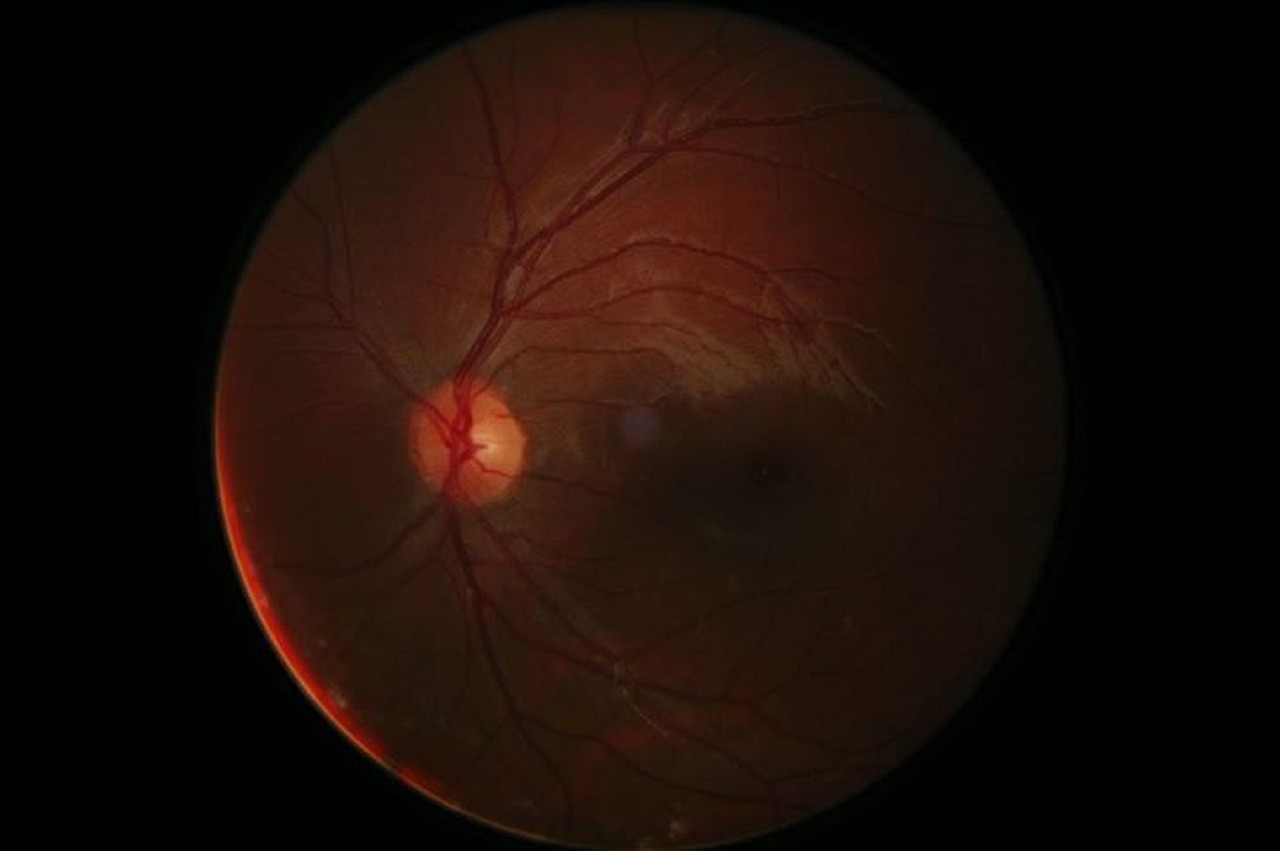

황반변성은 안구의 맥락막 아래에 위치한 황반부위의 변성으로, 주로 나이가 들면서 발생하는 혈관의 변화와 연관이 있습니다.

황반변성은 조금씩 진행되는 질환으로, 초기에는 증상이 미비하거나 무시될 수 있습니다. 그러나 질환의 진행에 따라 다음과 같은 증상이 난타날 수 있습니다.

1. 시력 저하: 가장 일반적인 증상으로, 중심 시야의 흐릿함, 흐린점 또는 흐릿한 영역이 있는 것으로 나타날 수 있습니다. 또한, 작은 글씨를 읽는 것이 어렵거나, 멀리 있는 물체를 인식하기 어려울 수 있습니다.

2. 중심 시야 손상: 황반 변성 환자는 중심 시야를 잃을 수 있습니다. 이는 중앙부에서 시작하여 점차 진전되는데, 가려짐, 흐림 또는 흐려진 영역이 중앙 시야를 가로지를 수 있습니다. 이로 인해 세부 사항이나 얼굴 인식, 읽기 등의 작업이 어려울 수 있습니다.